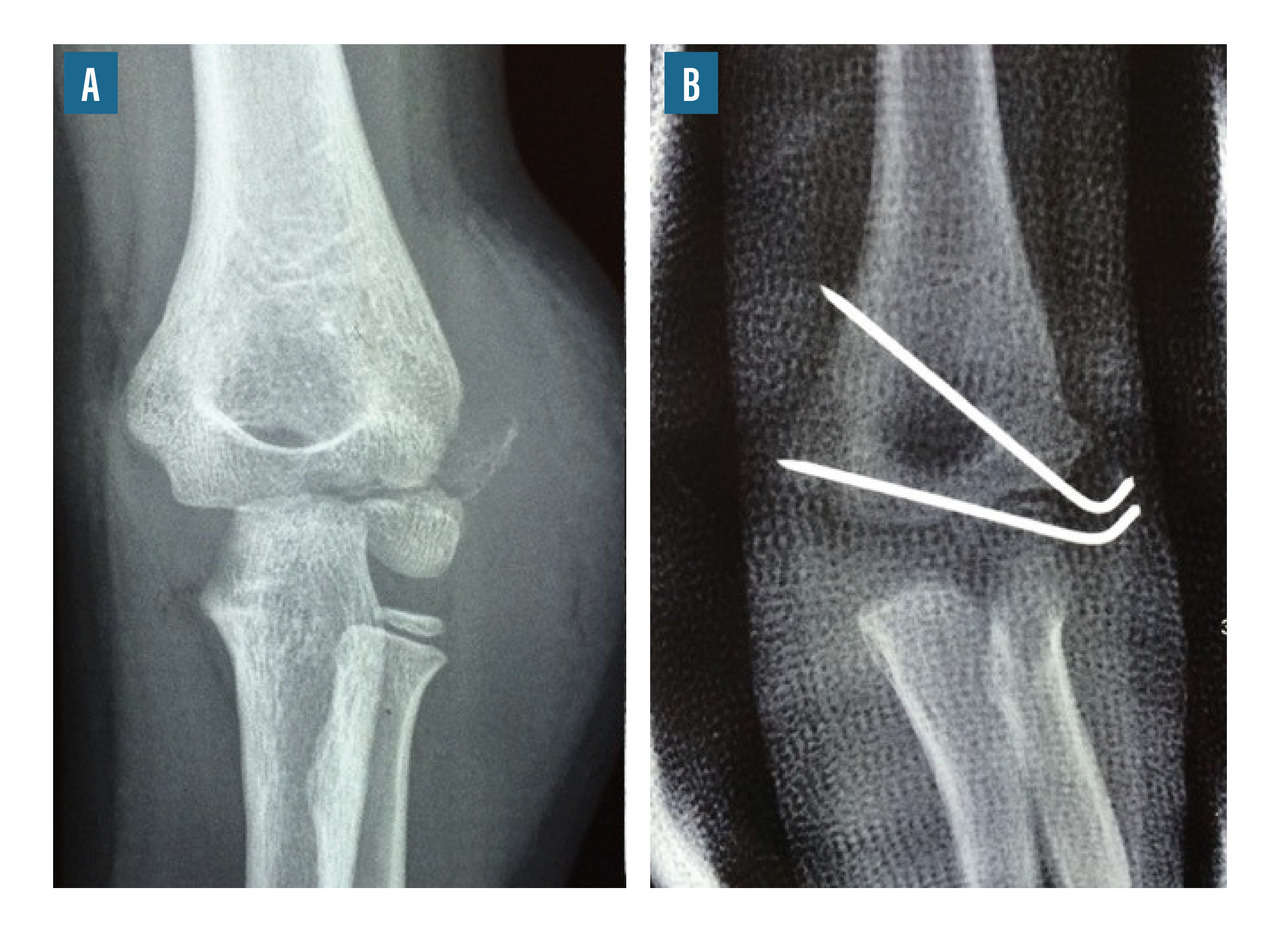

• le brochage direct (fig. 8) ;

Les fractures du coude de l’enfant sont parmi les plus fréquentes en traumatologie pédiatrique ; elles représentent environ 8 % des fractures de l’enfant, avec un pic de fréquence entre 5 et 9 ans. Elles sont souvent synonymes de prise en charge chirurgicale.

La répartition anatomique de ces fractures est la suivante : 44 % de fractures supracondyliennes, 22 % de fractures du condyle latéral, 10 % de fractures de l’olécrâne, 7 % de fractures de l’épicondyle médial (épitrochlée), 5 % de fractures du col du radius ou de la tête radiale, 5 % de lésions de Monteggia (fracture de l’ulna associée à une luxation de la tête radiale). Ces fractures ne sont pas de diagnostic radiographique facile, surtout chez l’enfant jeune dont les différents repères osseux ne sont pas forcément visibles sur la radiographie (maquette cartilagineuse du coude encore importante).

Le traitement chirurgical peut nécessiter un abord chirurgical, notamment dans les cas de fractures articulaires (fracture du condyle latéral, fractures intercondyliennes). Dans les autres cas, il s’agit habituellement de réductions orthopédiques maintenues par des broches ou un simple plâtre.